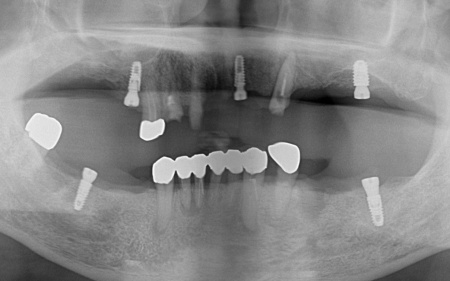

次に上下顎に装着するため、チタン床を使用した金属床義歯を作製しました。

また、上顎は残存歯が少ないためすべてを覆う総入れ歯で、下顎は前歯がしっかり残っているため部分入れ歯の形で作製しました。

完成した入れ歯を装着していただき、噛み合わせや義歯の安定性、見た目の仕上がりに問題がないことを確認して、治療を終了しています。

噛む機能の回復と自然な見た目の両方を実現するため、インプラントオーバーデンチャーによる治療を提案しました。

インプラントオーバーデンチャーとは、顎の骨に埋め込んだインプラント(人工歯根)を支えとして、取り外し可能な義歯を装着する治療法です。